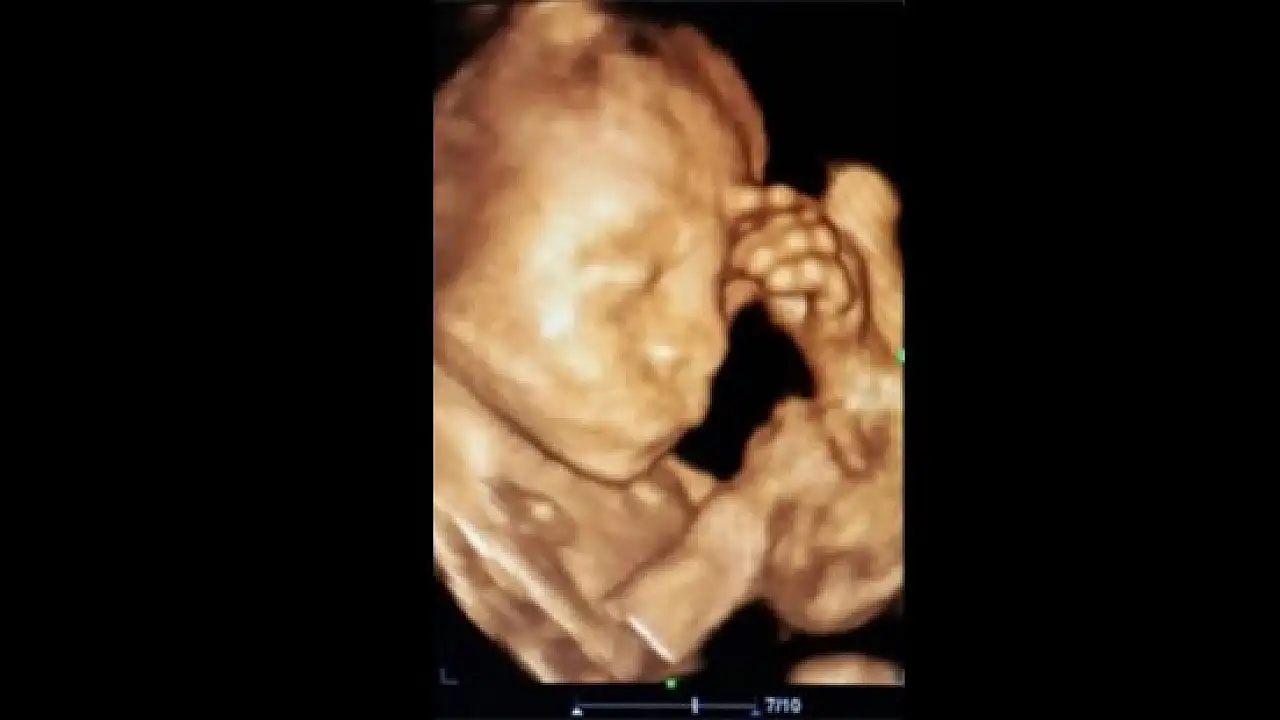

Konya’nın Ereğli ilçesinde önceki gün sosyal medyada paylaşılarak ilgi çeken, ultrasonda düşünür vaziyette görüntü veren bebeğin annesi Beyhan Öztürk, “Çocuğum doğduktan sonra havale geçirir mi diye sürekli düşünüyorum. Bebeğimin benim gibi fazla düşünmesini istemiyorum” dedi.

Ereğli’de önceki gün Kadın Hastalıkları ve Doğum Uzmanı Op. Dr. Kadriye Turgut tarafından sosyal medyada paylaşılan 23 aylık düşünen bebeğin annesi Beyhan Öztürk, bebeğinin havale geçirmesinden korktuğunu söyledi. Öztürk, doktorun kız dediği doğacak olan bebeğin beşinci çocuğu olacağını belirterek, “Dördüncü çocuğum doğduktan sonra havale geçirerek bizleri çok korkutmuştu. Ben de acaba bu çocuğum doğduktan sonra havale geçirir mi diye sürekli düşünüyorum. Doktor hanıma kontrole geldiğim zaman ultrasonda düşünüyor gibi çıkması beni sevindirdi. Bebeğimin benim gibi fazla düşünmesini de istemiyorum” dedi. Çıkan haberleri takip ettiğini de ifade eden Beyhan Öztürk, “Haberlerden sonra çok mutlu oldum. Çocuğum şu an 5 aylık ve sağlık durumu gayet iyi. Doktor hanıma da teşekkür ediyorum” şeklinde konuştu.

Op. Dr. Kadriye Turgut ise 5 aylık bebeğin sağlık durumunun gayet iyi olduğunu belirterek, “Anne gergin olduğu zaman bu gerginlik bebeğe de yansıyabilir. Bunun tıbbi bir kaynağı vardır. Anne daha önceki çocuğunun havale geçirdiğini ve bu bebeği için de endişelendiğini, bu yüzden de sürekli düşündüğünü söylüyor. Yaptığımız kontrollerde bebeğimizin hiçbir sıkıntısı görünmüyor. Ultrasonda bebeğin düşünüyor gibi oluşturduğu görüntü benim çok hoşuma gitti ve bu yüzden de sosyal medyada paylaştım” diye konuştu.